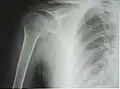

Рентгенограмма верхней части плечевой кости с выраженной хирургической шейкой -

Проксимальный эпифиз представлен головкой плечевой кости (лат. caput humeri), отделённой от диафиза анатомической шейкой (лат. collum anatomicum). Головка сочленяется с суставной впадиной лопатки, образуя плечевой сустав. За шейкой располагаются два бугорка (апофиза) — больший и меньший (лат. tuberculum majus et minus), между которыми проходит межбугорковая бороздка — место сухожилия длинной головки двуглавой мышцы плеча. Ниже бугорков, на границе с диафизом, проходит хирургическая шейка (лат. collum chirurgicum) — место наиболее частых переломов плечевой кости[3].

К 4—6 годам указанные центры сливаются в единую головку плечевой кости. Замещение метаэпифизарного хряща на границе проксимального эпифиза и диафиза костной тканью (синостоз) наступает в подростковом возрасте, благодаря чему продолжается рост кости в длину. На рентгенограмме ребёнка или подростка определяется характерный светлый участок на месте метаэпифизарного хряща, который может быть принят за перелом или трещину[4].